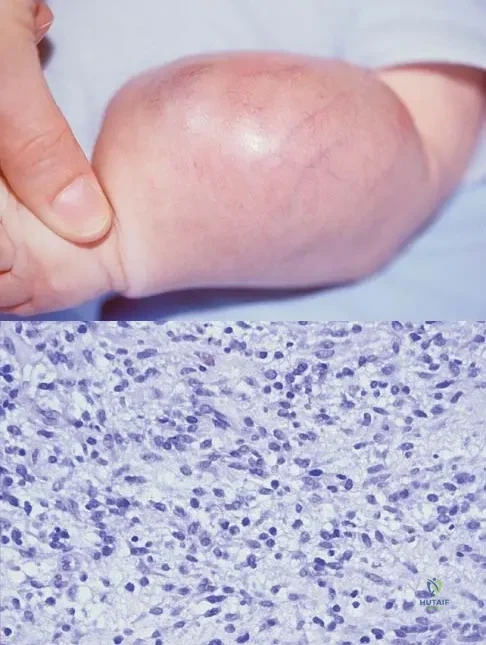

Question 21

An infant is born with a mass that involves both the volar and dorsal compartments of the left arm. A clinical photograph and biopsy specimen are shown in Figures 41a and 41b. What is the best initial course of action?

Explanation